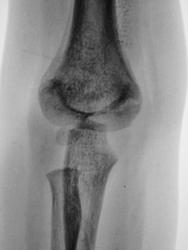

Ребенок. Снят гипс.

Первичный снимок.

3 года.

похоже на подвывых.

чрезмыщелковый перелом плечевой кости,c подвывыхom головки лучевой  кости

чрезмыщелковый перелом плечевой кости,c подвывыхom головки лучевой  кости с смешением вниз……

А Вы не допускаете,что могут быть прогрешности укладки, ротация предплечья например.

Обычный срастающийся с допустимым смещением чрезмыщелковый перелом. Подвывихов нет.